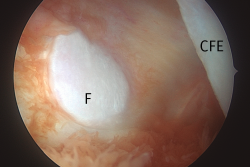

Esta técnica no forma parte de los gestos habituales durante una artroscopia rutinaria de rodilla, pero resulta muy útil en cirugías como la resección de ciertos tumores (destacando por su frecuencia la sinovitis villonodular pigmentada) (Figura 7), el abordaje a la fabela (Figura 8), la extracción de cuerpos libres o el reanclaje de avulsiones óseas de la inserción tibial del LCP. Además, la creación de este portal permite una buena visualización de la porción posterosuperior de ambos cóndilos femorales y de la cara posterior del LCP, del ligamento de Wrisberg, del tendón poplíteo y de la unión meniscocapsular de ambos meniscos(24)(Figuras 9 y 10).

Figura 8. Visión transescotadura, compartimento posterolateral, rodilla izquierda. Imagen de la carilla articular de la fabela, hueso sesamoideo articular incluido en el tendón del gastrocnemio externo. CFE: cóndilo femoral externo; F: fabela.